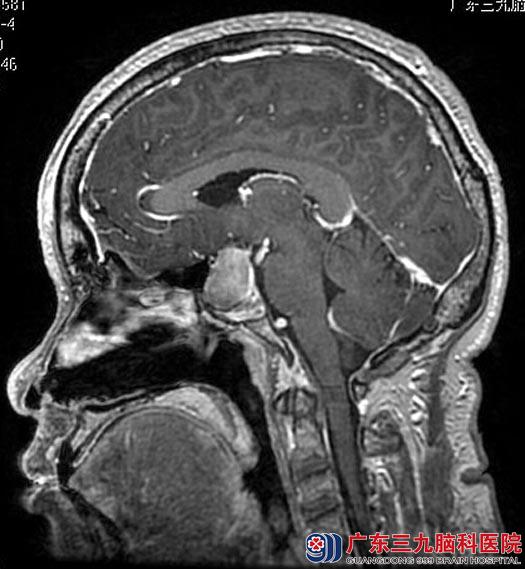

第二天,陈先生便带着母亲到当地医院,头颅CT检查提示鞍区占位,考虑垂体瘤可能性大。为进一步治疗,陈先生又带着母亲来到广东三九脑科医院垂体瘤诊疗中心。查体:脸面部颧骨增大、鼻梁增粗、四肢指端肥大,握拳不能,粗侧双眼视力0.8,视野基本正常。头颅MR检查提示:鞍区(鞍内为主)一结节状占位性病变,大小约1.8cm×2.4cm×2.4cm,右侧颈内动脉部分被包绕,行内分泌检查提示生长激素、泌乳素增高。